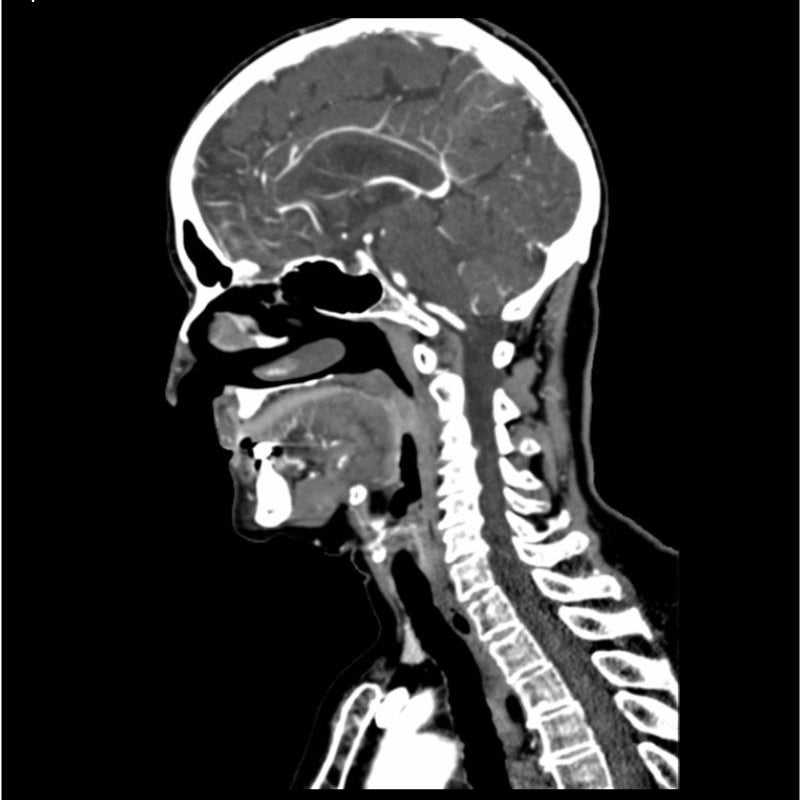

CTA Head and Neck Phantom for CT Scan and X-Ray Training

This phantom simulates a contrast medium enhanced head in arterial phase (CT angiography). The neck and upper thorax are included up to the aortic arch and the fifth thoracic vertebra. The vertex is included until approximately 0.5 cm below skin level. The thoracic phantom section excludes shoulder and back parts that are typically not part of CTA examinations. The interncal carotid artery has calcifications on both sides with moderate stenosis on the right side. Otherwise, the phantom has no significant vascular pathologies.

The phantom can be used in CT (including CBCT) to evaluate and optimize CTA imaging performance and post-processing applications such as vessel segmentation, including AI-enabled applications. It is also nicely suited for training purposes. The phantom provides a detailed and realistic simulation of vascular structures, soft and bone tissue, including small details such as lymph nodes. Air voids are filled with a cellulose-polymer composite of approx. -160 HU.

- Size: Approx. 19 x 22 x 32 cm

Realistic simulation of head and neck vessels up to the aortic arch, bone and soft tissues.

Calcifications of the internal carotid artery at the carotid bifurcation on both sides with mild stenosis on the right side.